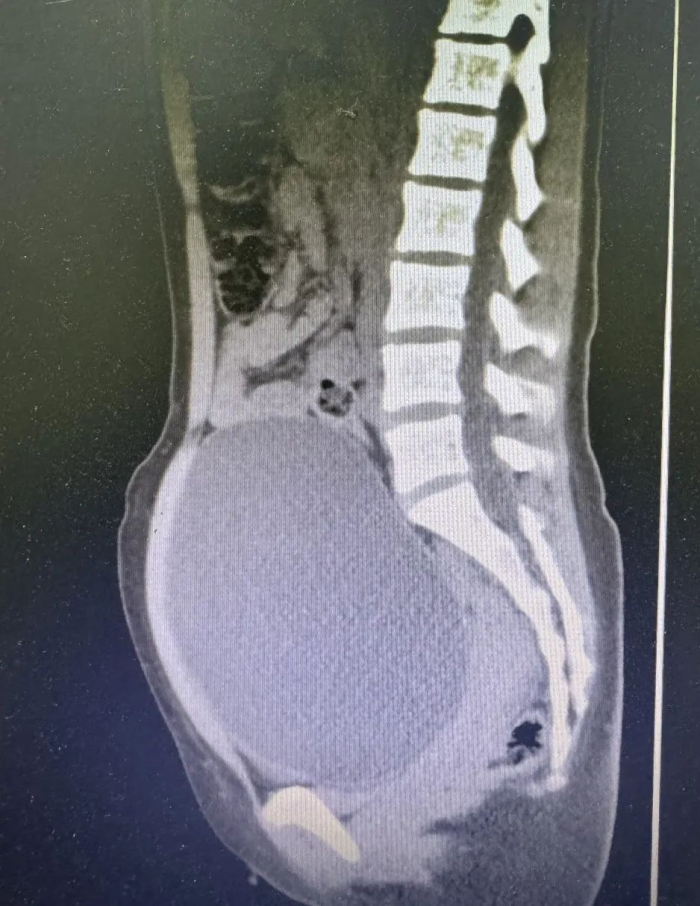

盆腔磁共振

前段时间患者不留意摔了一跤,之后下腹一直隐隐作痛,但是当时未在意,随着时间的流逝腹痛加剧,腹部包块越长越大,这才赶紧到县医院检查。医生通过追问病史,行盆腔磁共振检查提示巨大盆腔包块(大小约101mm×158mm×152mm),需要立即进行手术。